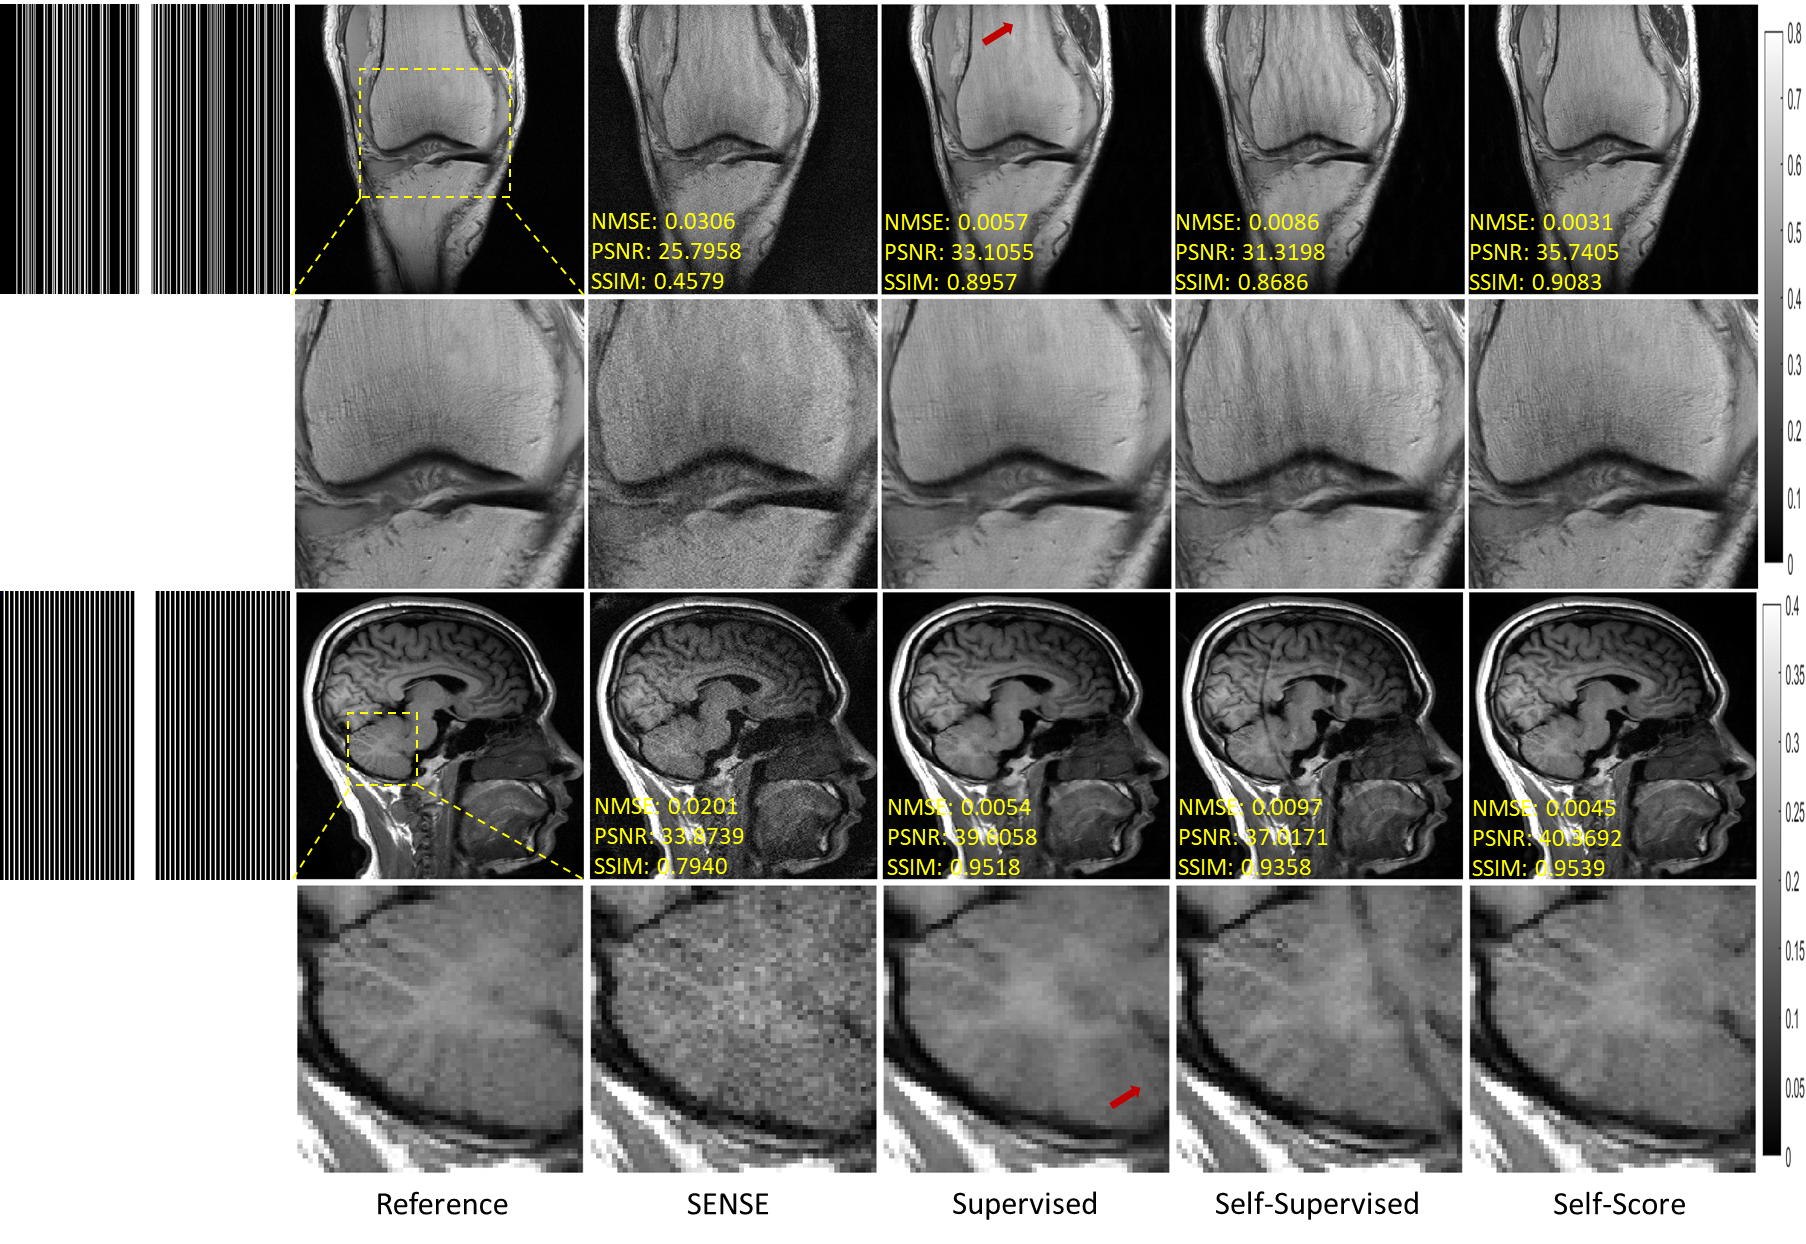

5.1 In-Distribution Performance

In this section, we tested the performance of various methods when sampling patterns and data types (anatomies) are consistent in training and testing. Figure 4 shows the reconstruction results for 5-fold random undersampling of fastMRI knee data and 4-fold uniform sampling of SIAT brain data. For the traditional PI method SENSE, the aliasing pattern remains in the reconstructed image and noise is amplified to the point that image details are obliterated. An obvious aliasing pattern remains in the reconstructed images for the self-supervised learning method. Although the noise is well suppressed for the supervised learning method, a tiny aliasing pattern remains in the reconstructed image where the red arrow points. The reconstructed image is also blurrier, and some texture information is lost from the visual perception. Our proposed method performs well in aliasing pattern suppression and image texture detail recovery. In particular, it is worth mentioning that the proposed fully-sampled-data-free method outperforms the conventional supervised DL method that requires a fully sampled training dataset, which is of practical significance.

Refer to caption

Figure 4: Reconstruction of the fastMRI knee (first two rows) and SIAT brain (last two rows) data at random sampling of R=5𝑅5R=5 and uniform undersampling of R=4𝑅4R=4, respectively. The values in the corner are NMSE/PSNR/SSIM values. Second and fourth rows illustrate the enlarged views. The grayscale of the reconstructed images is at the right of the figure.

The competitive quantitative results of the above methods are shown in Table 1. Our method consistently outperforms traditional SENSE, conventional self-supervised and supervised methods characterized by quantitative evaluations. The above experiments confirm our method’s competitiveness under consistent training and testing environments.